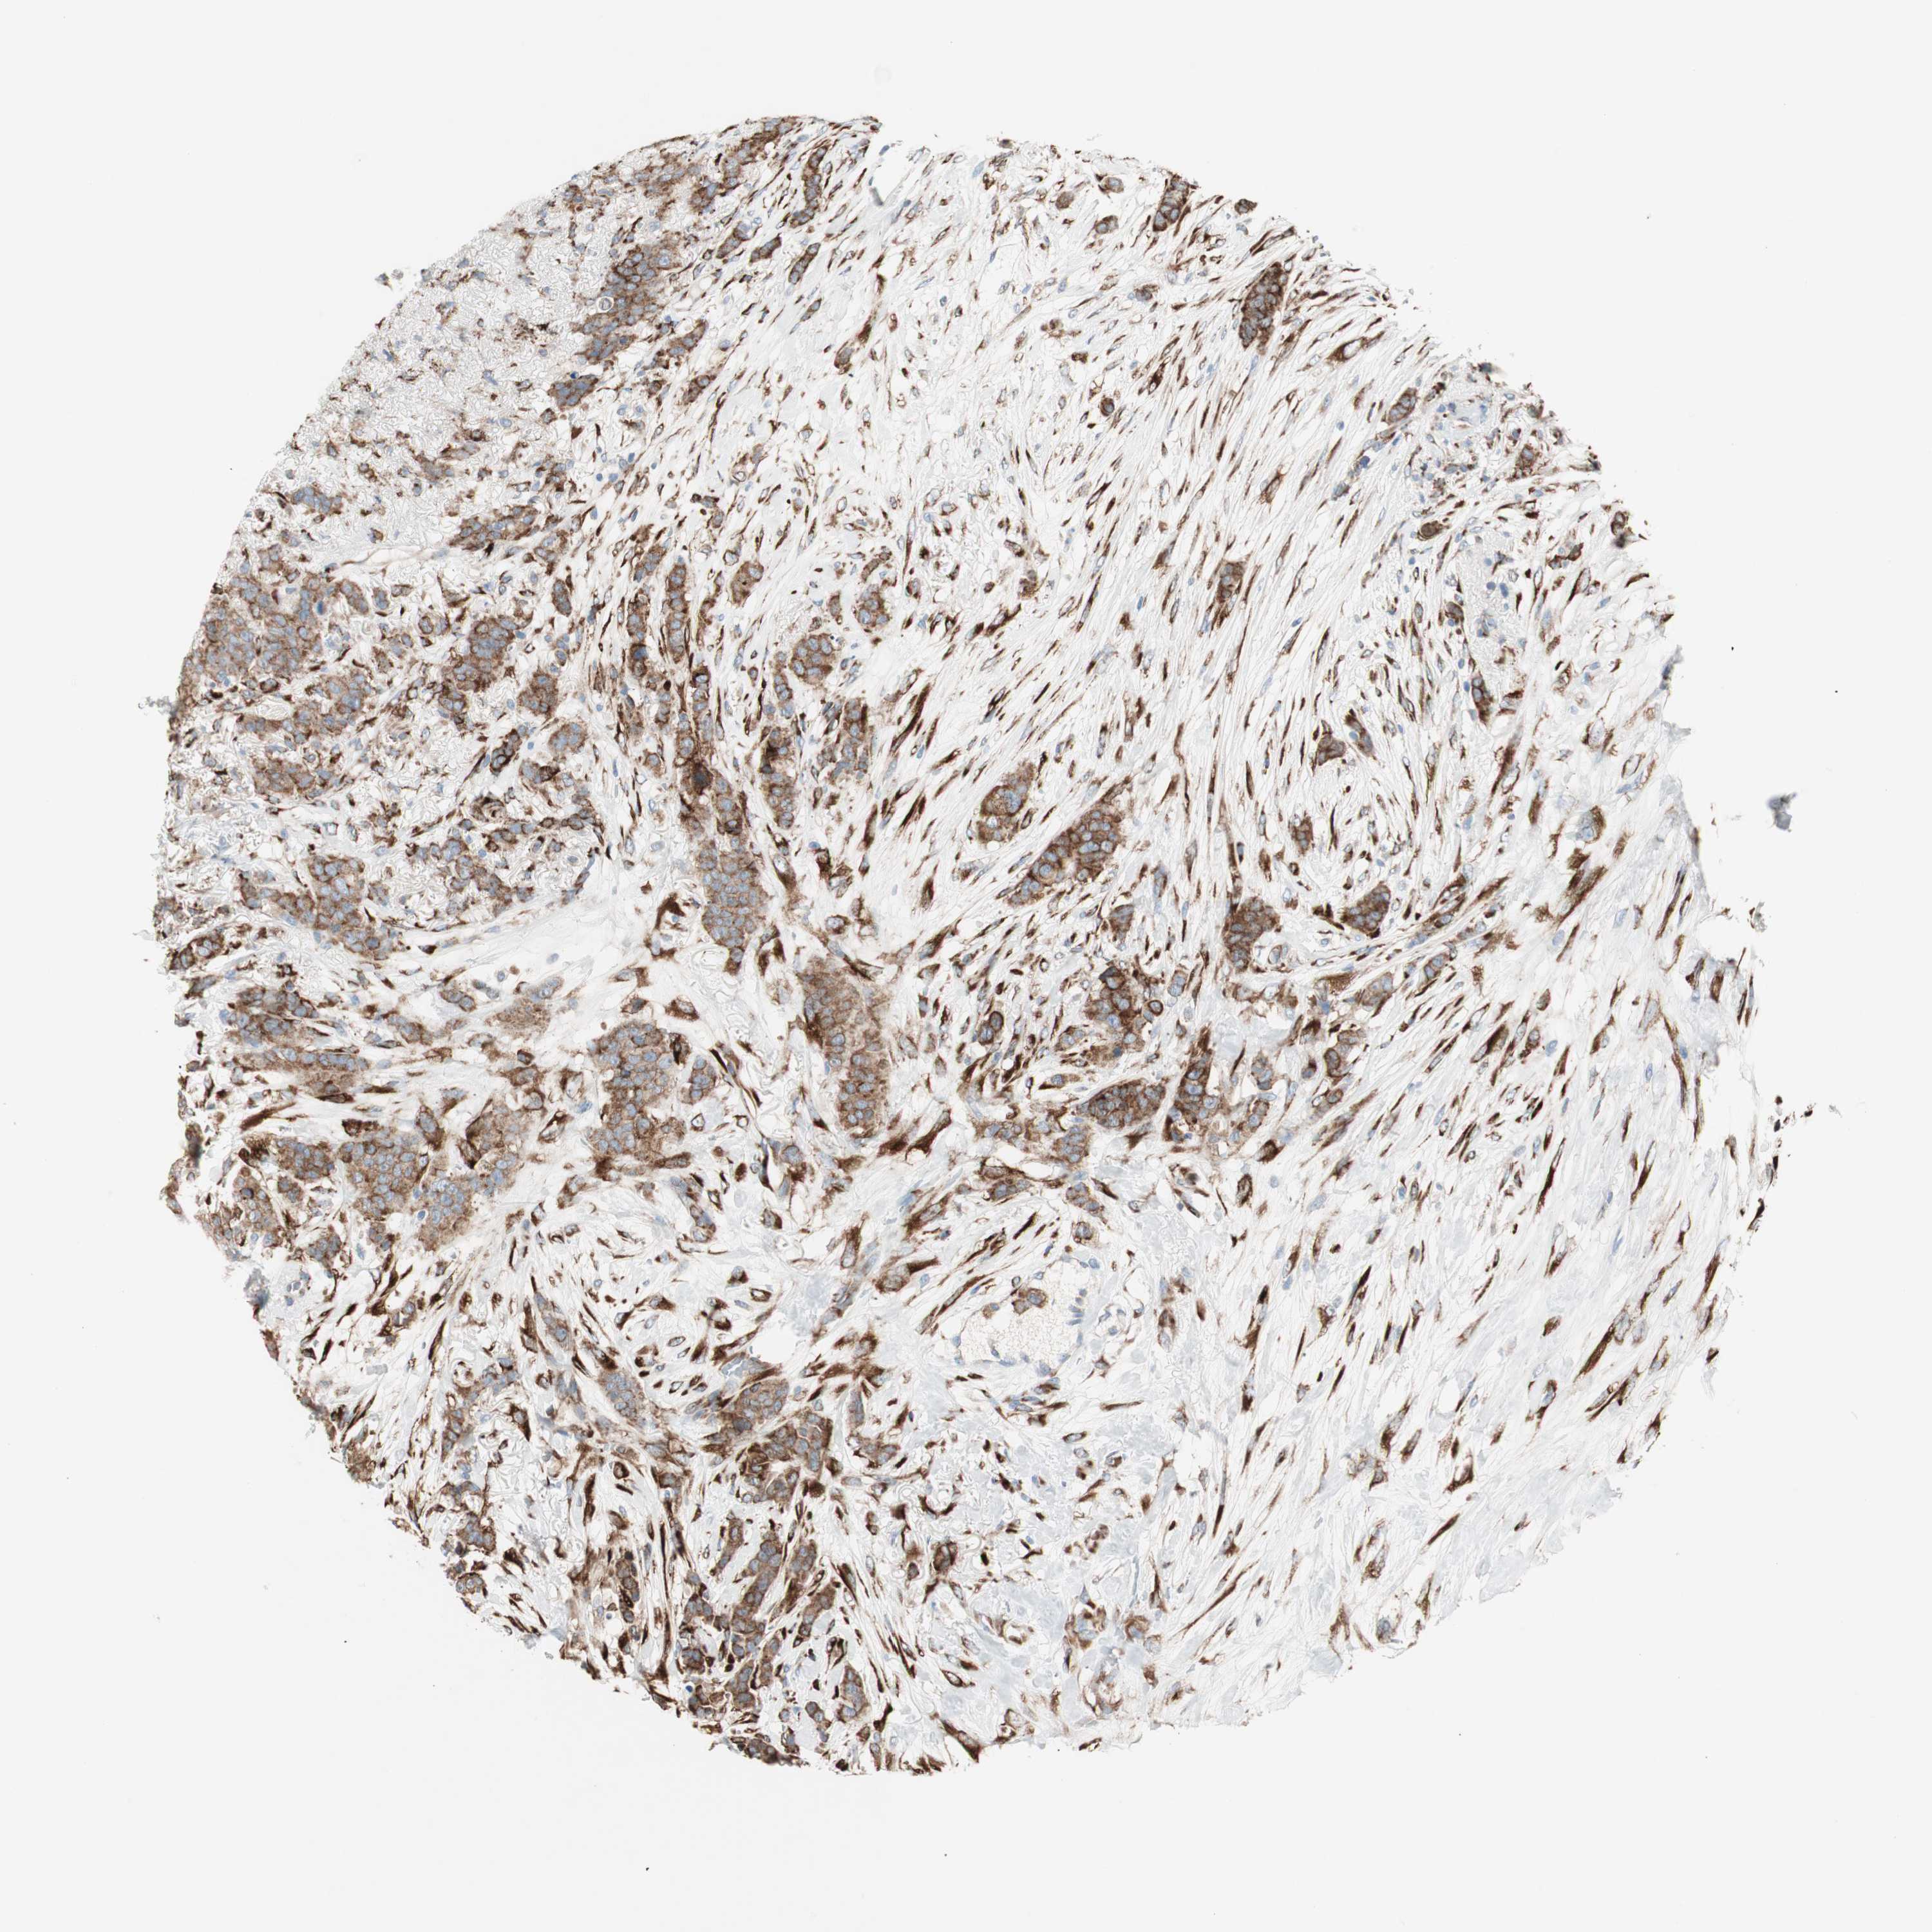

CANCER BREAST CANCER Show tissue menu

BRCA TCGA BRCA VALIDATION PROTEIN EXPRESSION